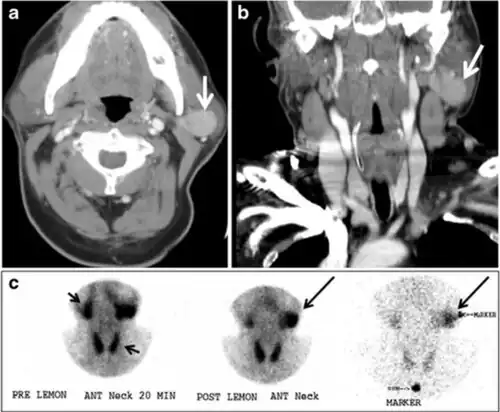

Fig. 17. Ectopic thyroid on the left parotid gland with a palpable left parotid mass in a 69-year-old male patient. a, b Axial and coronal enhanced neck CT scan demonstrates well-defined homogeneous enhancing mass (white arrows) within the left parotid gland with preserved surrounding fat planes. It also shows a normal thyroid in normal position in the lower neck. c Image taken 20 minutes after 5 mCi injected Tc99m-Pertechnetate shows normal thyroid uptake of tracer and physiological uptake in the salivary glands (short black arrow). There is a distinct focus of abnormal tracer accumulation in the left parotid/submandibular region. Patient was given lemon juice with evident normal washout from the salivary glands and relative retention by this abnormal focus (long black arrow).[1] -